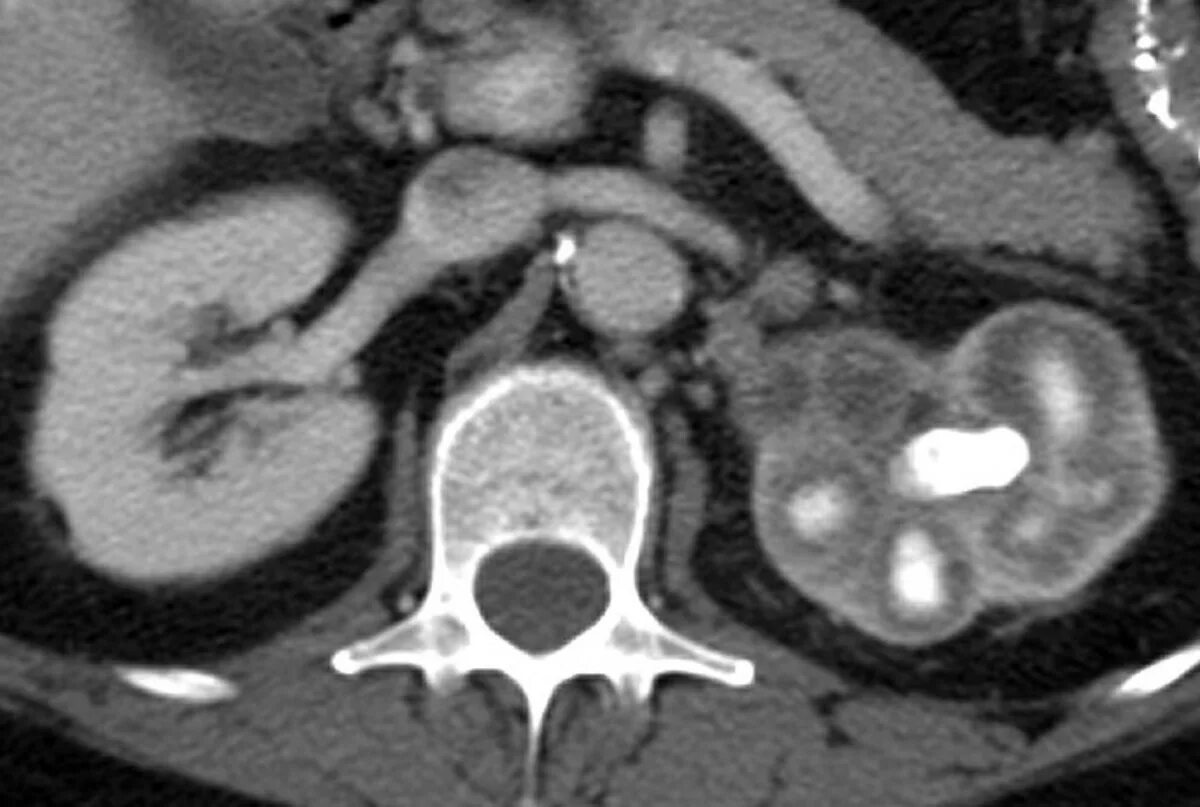

Пиелонефрит кт